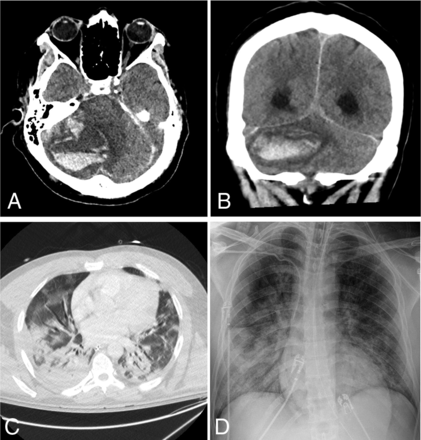

Of the 24 patients with acute neuroimaging findings, 7 patients were found to have intracranial hemorrhage (Fig 1), 7 patients were found to have acute infarction (Fig 2), 6 patients were found to have leukoencephalopathy (Fig 3), 3 patients had intracranial hemorrhage and infarction, and 1 patient had intracranial hemorrhage, infarction, and leukoencephalopathy (Table 2). Sixty-nine patients did not have acute neuroimaging findings (Fig 4). There was no significant difference (P = .225) between the distribution of Radiological Society of North America categories of chest CT findings between patients without acute neuroimaging findings (n = 66) and those with acute neuroimaging findings (n = 14), with the “typical” category being the most prevalent in both groups (Table 2).21

A 42-year-old man presented with hypoxemic respiratory failure. Non-contrast-enhanced axial (A) and coronal (B) CT head images demonstrate a new, large, right cerebellar intraparenchymal mixed-attenuation hematoma suggestive of hyperacute or active hemorrhage. C, Chest CT of the patient demonstrates bilateral consolidation and ground-glass opacities involving all lobes, with a CCS score of 18. D, Portable chest radiograph demonstrates bilateral patchy air space opacities with a PXS score of 10.3.

An 85-year-old man presented with increasing shortness of breath. Non-contrast-enhanced axial CT of the head demonstrates multiple new foci of hypoattenuation within the bilateral frontal corona radiata (arrows on A) and left centrum semiovale (arrow on B), in keeping with acute infarcts. C, Chest CT of the patient shows diffuse bilateral, right greater-than-left, predominantly consolidation and ground-glass opacities as well as bilateral pleural effusions. The CCS score was calculated as 13. D, Portable chest radiograph demonstrates bilateral patchy opacities with a PXS score of 10.6.

A 64-year-old man presented with fever and shortness of breath. Axial FLAIR (A) and diffusion-weighted (B) images demonstrate extensive symmetric confluent T2/FLAIR signal abnormality and restricted diffusion involving the corona radiata bilaterally. C, Chest CT shows bilateral peripheral ground-glass opacities and a small amount of consolidation involving all lobes, with a CCS score of 15. D, Portable chest radiograph demonstrates bilateral lower-zone-predominant peripheral opacities with a PXS score of 8.8.